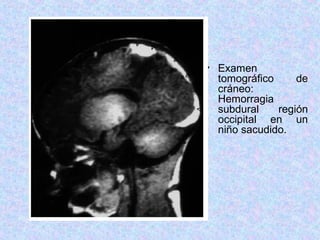

• Examen

tomográfico de

cráneo:

Hemorragia

subdural región

occipital en un

niño sacudido.

• Examen tomográfico de cráneo: Hemorragia subduralregión occipital en un niño sacudido.